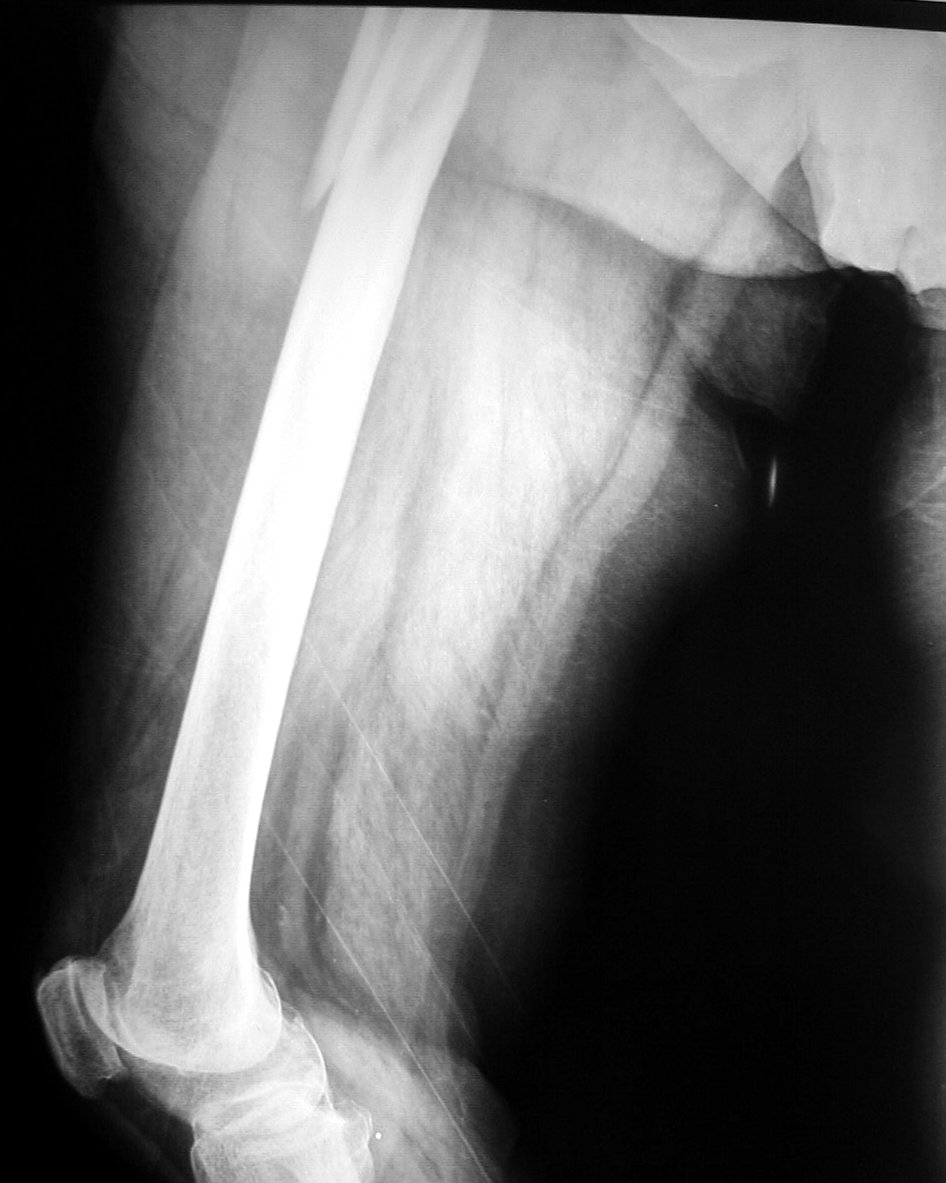

Fracturas: rotura total del hueso. La fractura puede ser

interna, si el hueso roto no rompe la piel y queda en el interior del

cuerpo, o externa, que provoca el desgarro de la piel y el hueso queda al

descubierto.